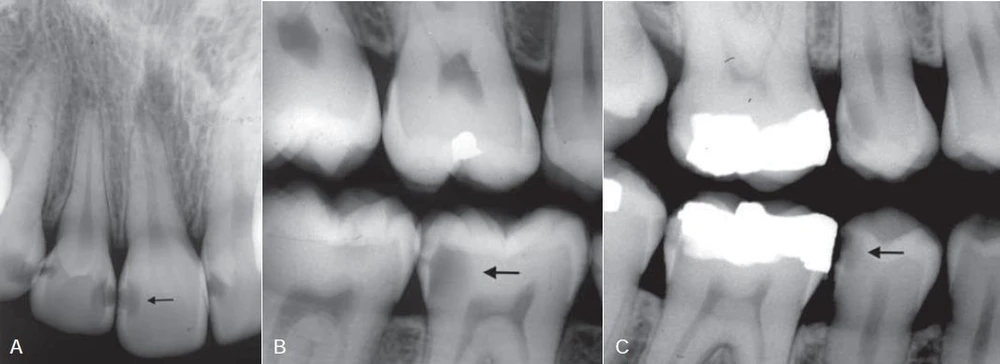

Hình ảnh X quang truyền thống của một tổn thương xuyên vào ngà răng là hình ảnh thấu quang với đáy rộng, thường nằm bên dưới một rãnh, trong khi đó ở men răng chỉ có những thay đổi nhỏ hoặc không thay đổi gì rõ rệt. Tổn thương mặt nhai càng sâu thì càng dễ phát hiện trên X quang.

Hình 14. Tổn thương sâu răng mặt nhai khảo sát trên phim X quang

Những sai sót khi phân tích tổn thương ngà răng ở mặt nhai bao gồm việc hình ảnh những hố mặt nhai chồng lên nhau cùng có liên quan hoặc không có liên quan đến tổn thương sâu răng hoặc một miếng trám composite, vốn nhìn giống như tổn thương mặt nhai hoặc một rãnh sâu. Việc khám trực tiếp trên lâm sàng thường loại trừ đi những nhầm lẫn như vậy. Khi tổn thương mặt nhai khu trú ở phần men răng, phần men xung quanh thường che mất tổn thương này. Khi quá trình sâu răng tiến triển, có một đường thấu quang lan rộng dọc theo đường nối men ngà. Khi tổn thương lan rộng vào phần ngà, bờ giữa sâu răng và phần ngà lành mạnh có thể chồng lên nhau và che mất đường thấu quang tại đường nối men ngà. Do đó, đối với những tổn thương còn nông thì tỉ lệ dương tính giả có thể cao ngang với tỉ lệ âm tính giả. Một kết quả âm tính giả có thể không phải là một sai lầm nghiêm trọng do trong hầu hết các trường hợp sâu răng tiến triển chậm và tổn thương được phát hiện ở một thời gian sau đó. Một kết quả dương tính giả có thể dẫn đến việc bề mặt răng lành mạnh bị xâm phạm không thể hồi phục được. Ngoài ra, khi có một sự khác biệt về mật độ rõ rệt, chẳng hạn như giữa men và ngà, thì có thể có một vùng thấu quang ngay gần men răng. Đây là một ảo giác quang học gọi là dải Mach (hình minh hoạ bên dưới). Nó có thể tạo nên nhiều kết quả dương tính giả; vì vậy, nên theo dõi những trường hợp này và từ chối việc điều trị can thiệp.

Cân nhắc việc tạo xoang và điều trị

Khi một tổn thương mặt nhai mở rộng xuyên qua ngà răng, phần men răng sẽ bị yếu, và cuối cùng lực ăn nhai sẽ gây sụp phần men này, tạo thành một xoang sâu. Khi thấy lỗ sâu trên lâm sàng thì thường tổn thương đã vào ngà răng, nếu những thông tin cho thấy tổn thương lan rộng đến gần buồng tuỷ thì cần chụp X quang để kiểm tra. Nếu không có lỗ sâu nhưng các hố rãnh mặt nhai bị đổi màu thì cần chụp X quang kiểm tra. Tổn thương ngà răng không có lỗ sâu rõ ràng trên lâm sàng nhưng lại có những thay đổi thấu quang trên X quang thì chứng tỏ sâu răng đã vượt qua đường nối men ngà và cần điều trị phục hồi bằng miếng trám.

Hình 15. Tổn thương sâu răng mặt ngoài (mũi tên)